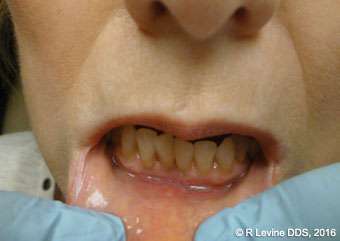

In comparison with conventional scalpel, the use of the CO2 laser in oral soft tissue surgeries offers several benefits. Among these benefits are cutting in a non-contact mode (which helps to avoid mechanical trauma to the tissue) and without bleeding or the need for sutures, precise tissue removal, and minimized postoperative pain, edema, and inflammation. The use of a CO2 laser on the oral soft tissue has no known contraindications or side effects.[5] A substantial body of peerreviewed literature describes the excellent hemostatic capacity of the CO2 laser as a useful instrument for oral surgery in patients with hemorrhagic disorders or undergoing antithrombotic therapy (Figures 3A-3B).[5-8] Due to the hemostatic ability of the CO2 laser, intraoral surgical wounds often can be left to heal by secondary intention without placing sutures or dressing (as in Cases 3, 5, 7, and 8 described in this article).[10] For example, the patient in Case 1 (Figures 3A-3C) wanted to have a vascular lesion (capillary hemangioma on the lip) removed. The risk of intraoperative hemorrhage was elevated by the fact that the patient had been taking blood thinning agents for his atrial fibrillation condition. In addition, the lesion was located in the area where successful cosmetic outcome was important; therefore, it was crucial to have good visualization of the operatory field. Efficient intra-operative hemostasis provided by the CO2 laser allows for more precise and accurate tissue removal due to the improved visibility of the surgical field (Figure 3B).[9] In this case, the CO2 laser enabled the clinician to achieve the best results in a short period of time. No sutures were placed, and a thin layer of char was created to protect the surgical site. The recovery was uneventful. Figure 3C shows the completely healed surgical site at 1 month postoperatively.

Figures 4A-4B, 5A-5B, 6A-6C, 7B-7C, and 8A demonstrate the enhanced hemostasis ensured by the LightScalpel CO2 laser. In Case 2, the patient had the vestibular extension procedure performed, and the hemorrhage was very well controlled, enabling the clinician with utmost precision. In Case 3, the bloodless excisional biopsy of fibroma was performed. Case 4 is a stage II implant uncovering procedure. This surgery requires both special accuracy and the well-controlled depth of laser energy penetration as well as enhanced hemostasis. No blood was present at any point. The implant was uncovered in approximately 30 seconds. In connection with implant uncovering, it should be mentioned that the recent study on the 10,600 nm CO2 laser removal of biofilm from titanium implant surfaces[11] reported that this laser wavelength does not affect titanium or titanium oxide (most common implant materials) and is therefore safe to use around implants. Case 5 shows a LightScalpel CO2 laser lingual frenectomy in a 7-year-old patient. Surgery is performed in a highly vascularized area where bleeding was well controlled. Finally, Case 6 is the ablation of the inflamed operculum. Figure 8A demonstrates the immediately postoperative view with excellent hemostasis.